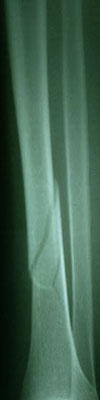

Fraktur tulang adalah cedera serius yang sering terjadi akibat berbagai kecelakaan atau aktivitas fisik yang berlebihan. Identifikasi fraktur tulang dengan cepat dan tepat sangat penting untuk menentukan perawatan yang sesuai. Salah satu pendekatan untuk mengidentifikasi fraktur tulang adalah melalui analisis citra radiografi. Dalam artikel ini, akan dijelaskan bagaimana pengolahan citra, khususnya dengan metode deteksi tepi Canny dan ekstraksi ciri menggunakan metode moment invariant, dapat digunakan untuk identifikasi fraktur tulang tibia dan fibula dengan bantuan algoritma Support Vector Machine (SVM).

Deteksi tepi adalah langkah kunci dalam identifikasi fraktur. Metode deteksi tepi Canny adalah salah satu teknik yang umum digunakan untuk menemukan tepi dalam citra. Ini bekerja dengan mengidentifikasi perubahan tajam dalam intensitas citra, yang sering terjadi di sekitar tepi objek. Hasil dari langkah ini adalah citra dengan tepi yang lebih tajam dan jelas.

Setelah deteksi tepi selesai, langkah selanjutnya adalah segmentasi citra. Dalam konteks ini, kita ingin mengisolasi area di sekitar fraktur tulang tibia dan fibula. Hal ini dapat dilakukan dengan menggunakan teknik segmentasi berdasarkan intensitas piksel atau dengan teknik lain yang sesuai.

Setelah citra telah di-segmentasi dengan benar, kita dapat melanjutkan dengan ekstraksi ciri. Moment invariant adalah salah satu metode ekstraksi ciri yang berguna dalam menggambarkan bentuk objek pada citra. Metode ini menghasilkan serangkaian nilai yang tidak berubah terhadap perubahan dalam skala, rotasi, atau translasi objek. Ini adalah fitur yang berguna untuk membedakan fraktur tulang dari struktur tulang normal.